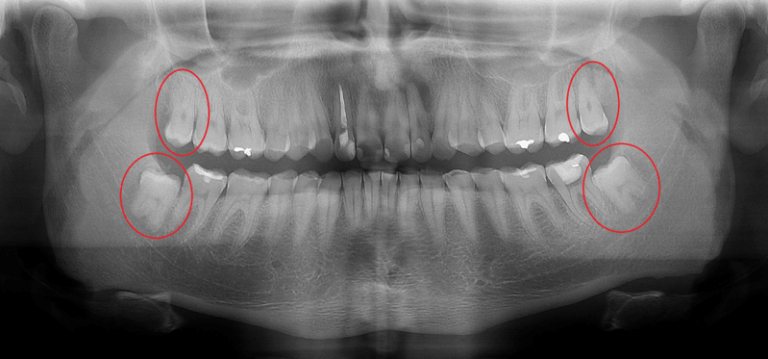

Contamos com exames realizados no próprio local e uma equipe experiente, garantindo mais segurança em procedimentos cirúrgicos, como a extração do dente do siso.

radiografia-panoramica-dente-siso-botucatu

A avaliação inicial é realizada por profissionais com ampla experiência em diagnósticos e planejamento de tratamentos odontológicos. Durante a consulta, fazemos uma análise completa, utilizando tecnologia avançada como radiografia panorâmica e escaneamento intraoral para entender suas necessidades e recomendar o melhor plano de tratamento.